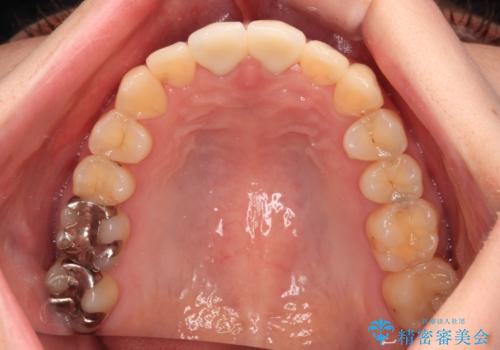

変色した前歯 オールセラミッククラウンにより審美歯科治療

- 神経を取り除いたことで経年変色した前歯2本を気にして来院された患者様です。

根管治療を行う必要はないと判断し、双方の歯にグラスファイバーを含有した土台を植立してオールセラミッククラウンにて補綴することとしました。

色調が周囲の歯とアウトともに、表面のつぎはぎや穴を封鎖した際の段差などが解消され、天然歯のような感触となりました。